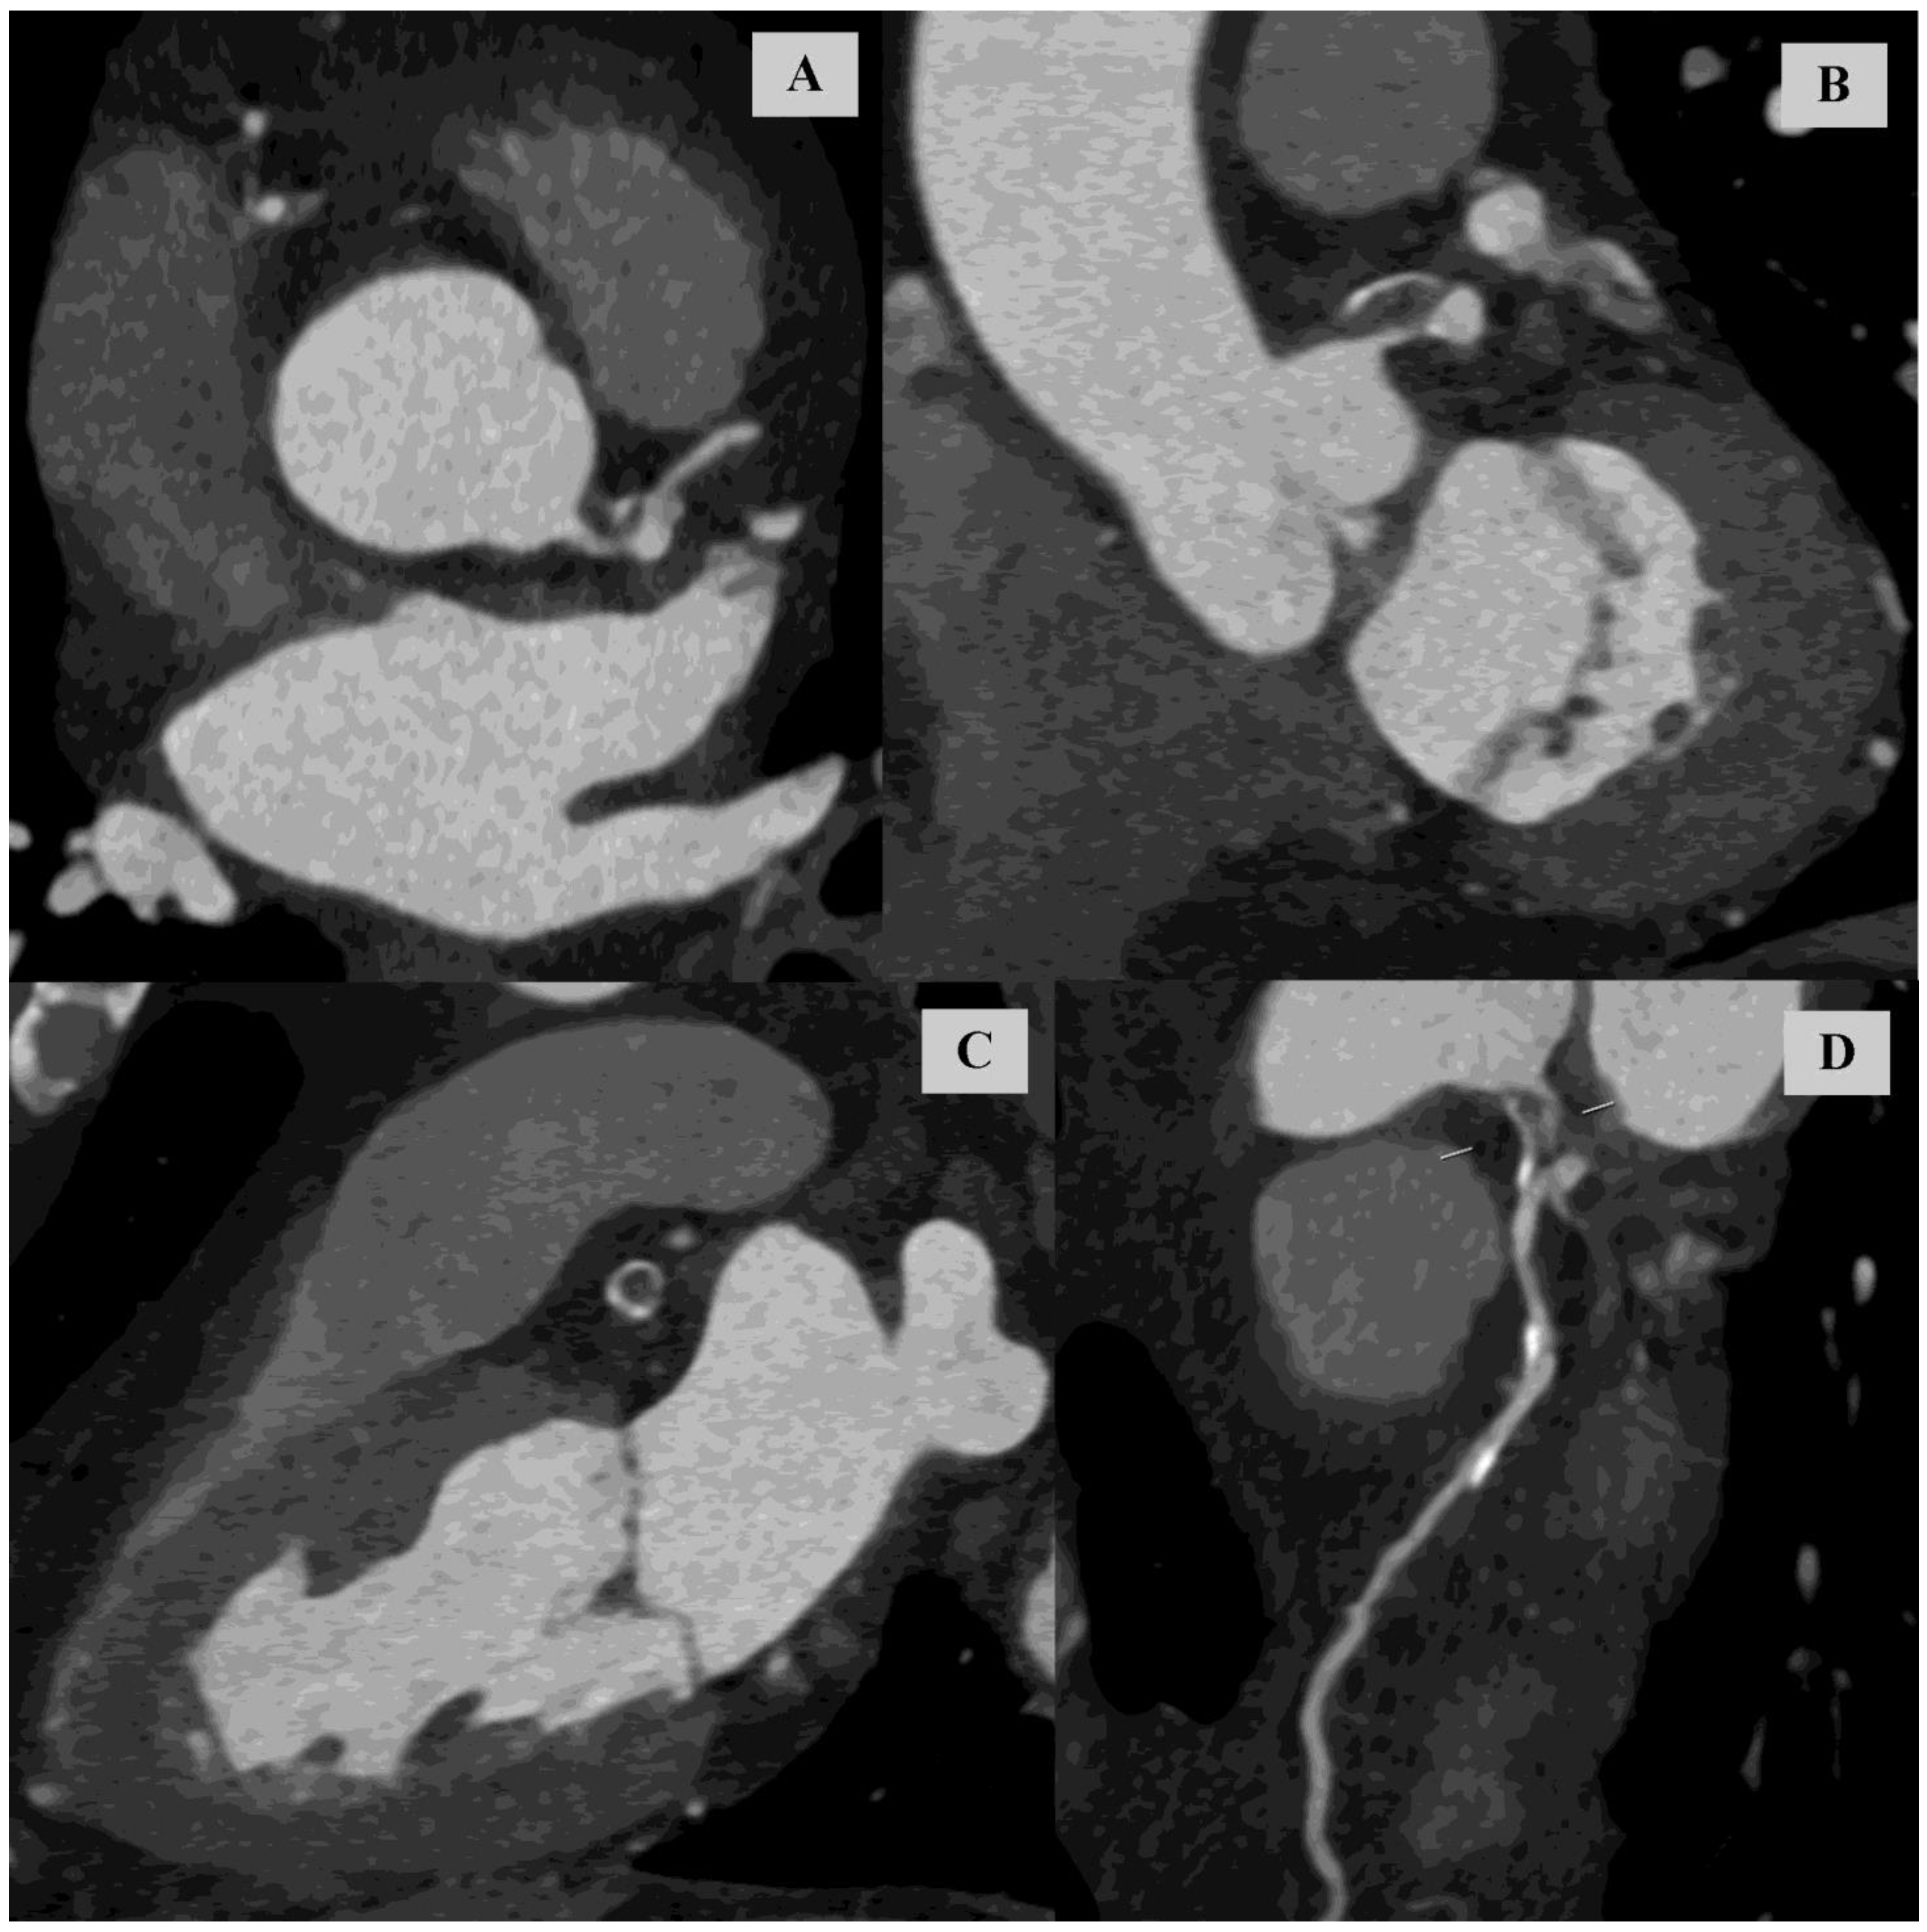

Kugel’s Artery in Coronary Computed Tomography Angiography in a Patient with Left Main Subtotal Stenosis

Gać, P.; Głuszczyk, A.; Plizga, J.; Bińczyk, W.; Dróżdż, O.; Poręba, R. Kugel’s Artery in Coronary Computed Tomography Angiography in a Patient with Left Main Subtotal Stenosis. Diagnostics 2024, 14, 2142. https://doi.org/10.3390/diagnostics14192142